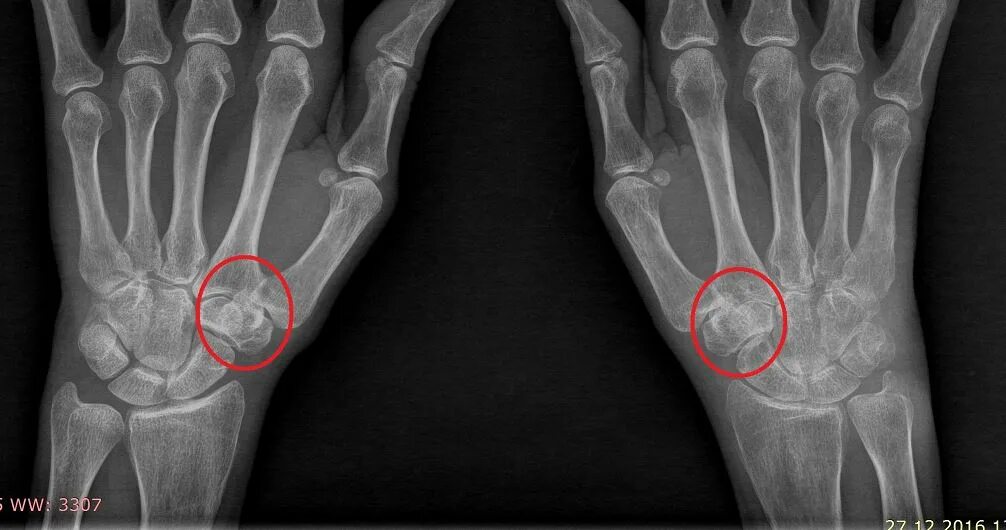

Снимок костей как называется